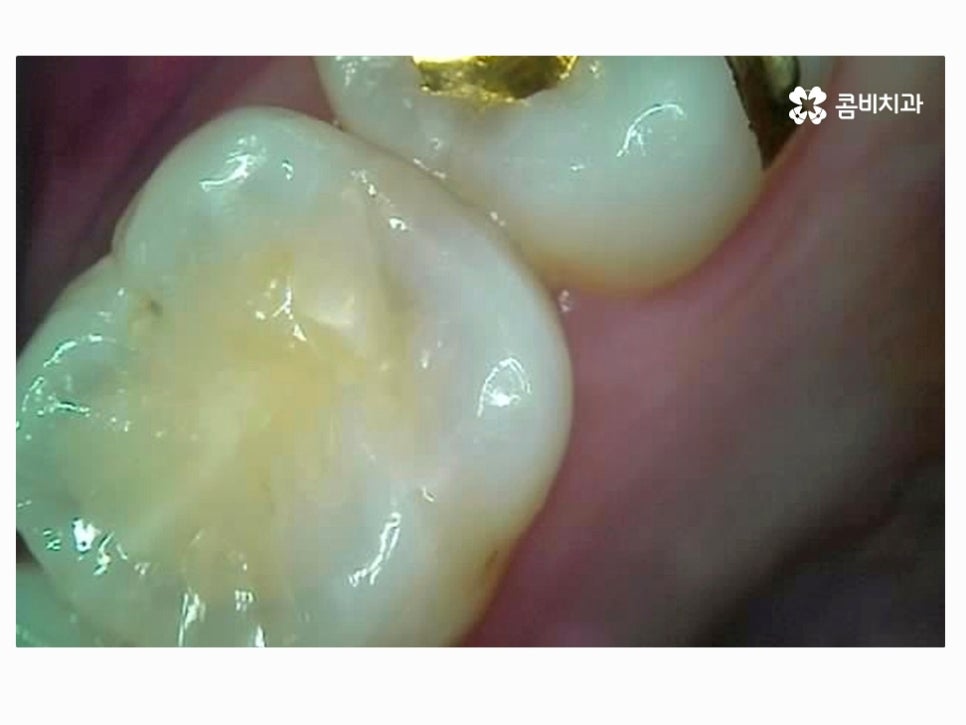

치아는 환자분들이 겉으로만 봐서는 건강한 상태인지 정확하게 알기 어려운데

위 치아 상태만 보더라도 만약 통증이나 이 시림 등을 겪고 있지

않다면 크게 문제가 있다고 느끼지 않을 분들이 많을 거예요.

다시 치아를 자세히 보면 마치 멍이 든 것처럼 살짝 검게 보이기도 하고

이미 환자분께서도 충치로 인한 통증을 호소하고 있는데요.